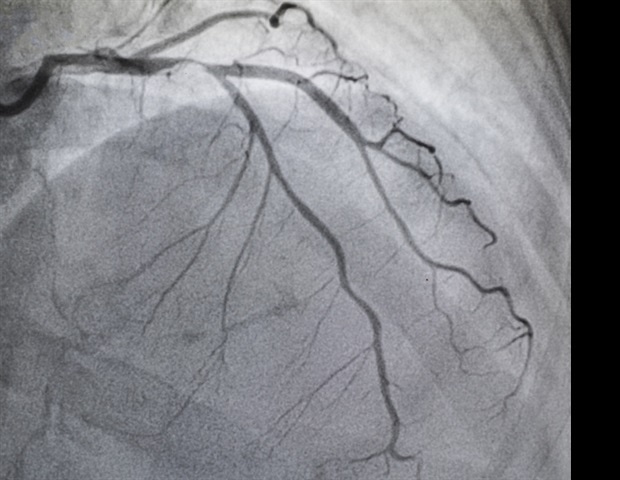

Οι ερευνητές παρουσίασαν τα ευρήματά τους σήμερα στο Συνέδριο της Εταιρείας Καρδιοαγγειακής Αγγειογραφίας και Παρεμβάσεων (SCAI) 2026 και στην Καναδική Ένωση Επεμβατικής Καρδιολογίας. Το TAVR είναι μια ελάχιστα επεμβατική διαδικασία που επιτρέπει την αντικατάσταση της αορτικής βαλβίδας μέσω ενός αιμοφόρου αγγείου, χωρίς να απαιτείται το άνοιγμα του θώρακα, σε αντίθεση με τη SAVR που προϋποθέτει τη διεξαγωγή ανοιχτής καρδιοχειρουργικής.

Το TAVR πλέον αποτελεί θεμέλιο της καρδιολογικής φροντίδας για εκατομμύρια ανθρώπους με ασθένειες των βαλβίδων της καρδιάς. Όμως, η πρόσβαση στις τελευταίες θεραπείες σε κάποιες περιοχές, κυρίως σε αγροτικές, μπορεί να καθυστερήσει την απαραίτητη φροντίδα. Οι γιατροί και οι εκπαιδευτές θα πρέπει να παρέχουν στοχευμένη εκπαίδευση και να κοινοποιούν νέες πληροφορίες, ώστε οι ασθενείς να κάνουν τις σωστές επιλογές και να διευρύνουν την πρόσβαση σε ελάχιστα επεμβατικές θεραπείες.